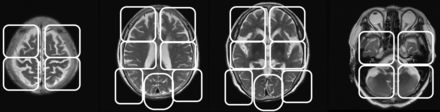

Two board-certified radiologists who are also nuclear medicine physicians with >10 years of experience in reading MR imaging and SPECT brain images and 2 years of experience reading ASL-MR imaging independently reviewed the images obtained in the present investigation without the clinical information of the patient. SPECT and ASL-MR imaging were shown with a section thickness of 6.6 and 6.4 mm, respectively. We used the scoring sheet shown in Fig 1 to assess 22 brain regions. The regions were located at the levels of the vertex, lateral ventricle, basal ganglia, and cerebellum. The raters scored each region by using a 4-point scale, in which zero indicated normal CBF; 1, a mild decrease; 2, a moderate decease; and 3, a severe decrease. The diagnostic confidence of AD was also scored between 0 and 4, in which 0 indicated definitely not AD; 1, probably not AD; 2, undetermined; 3, probably AD; and 4, definitely AD. ASL-MR images were displayed in gray-scale and in color-scale fused with T1-weighted images. SPECT images were displayed in color.

The regions used for scoring brain images. We evaluated 22 regions located at the levels of the vertex, lateral ventricle, basal ganglia, and cerebellum. The raters scored each region with a 4-point scale, where 0 is a normal CBF, 1 is a mild decrease, 2 is a moderate decease, and 3 is a severe decrease.